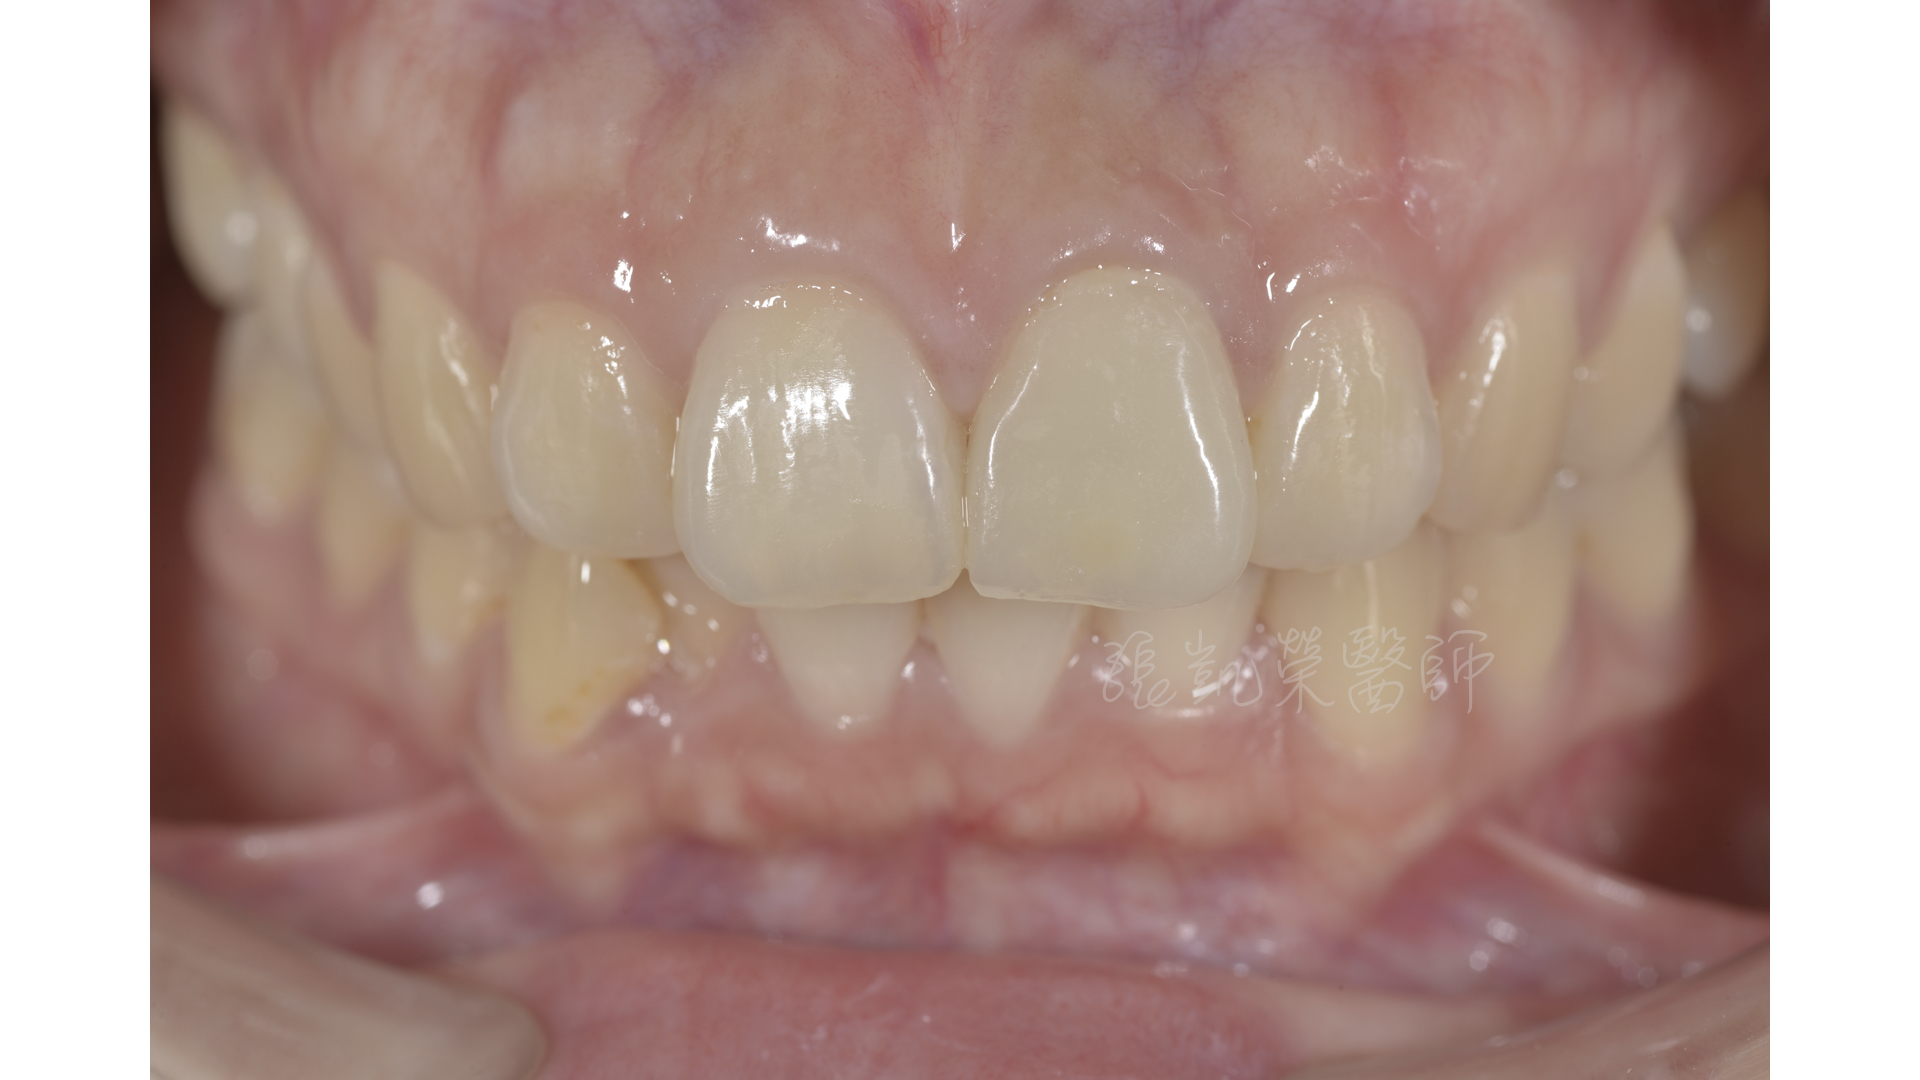

齒內美白與碳纖維柱釘治療後